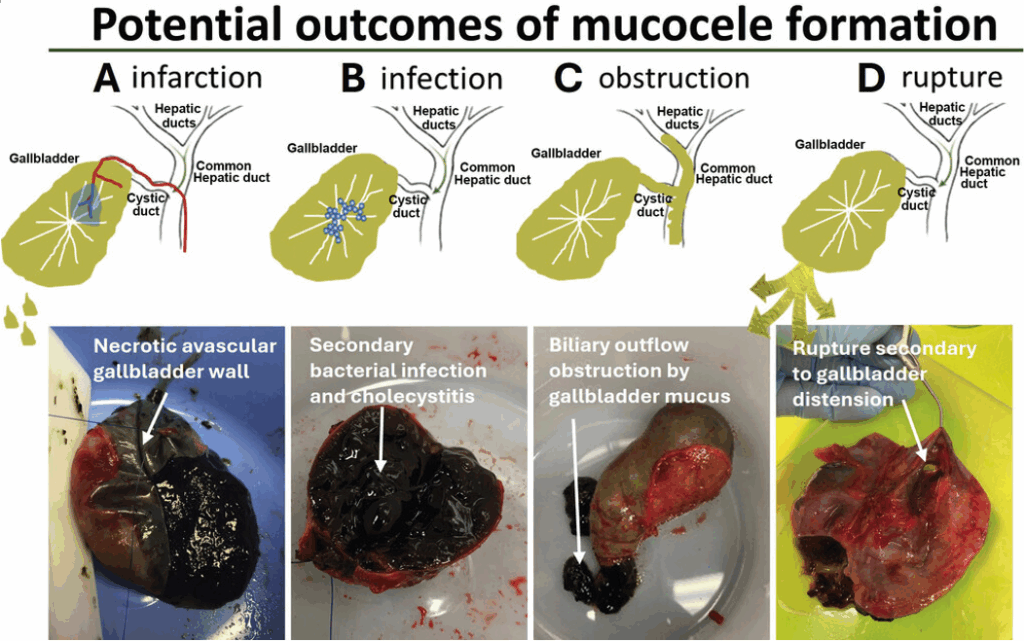

질환이 진행되어 담낭이 과도하게 팽창하면, 담낭벽으로 가는 혈류가 줄어들어 담낭 괴사가 일어나거나 이차적인 세균 감염 및 담즙 배출 장애를 유발합니다. 이는 결국 전신 상태를 급격히 악화시키며 생명을 위협하는 응급 상황으로 이어질 수 있습니다.

담낭에 염증과 괴사가 진행되면 결국 담낭 파열 이라는 최악의 상황에 이를 수 있습니다. 이때 유출된 담즙은 복강 내로 퍼져 복막염이나 췌장염 같은 심각한 전신 장기 손상을 일으킵니다. 이는 아이의 생명을 즉각적으로 위협하는 응급 상황이기에, 골든타임을 놓치지 않는 긴급 수술이 무엇보다 중요합니다.

설령 파열까지 진행되지 않더라도 안심할 수는 없습니다. 끈적하게 변한 점액질이 담관을 막아버리면 간에서 생성된 담즙이 배출되지 못해 심각한 전신 황달과 급성 간부전으로 이어질 수 있습니다.

Parkanzky MC, Grimes JA. Diagnosis and management of gallbladder mucocele formation in dogs. Vet Clin North Am Small Anim Pract. 2023;53(5):1109-1123. doi:10.1016/j.cvsm.2023.05.005